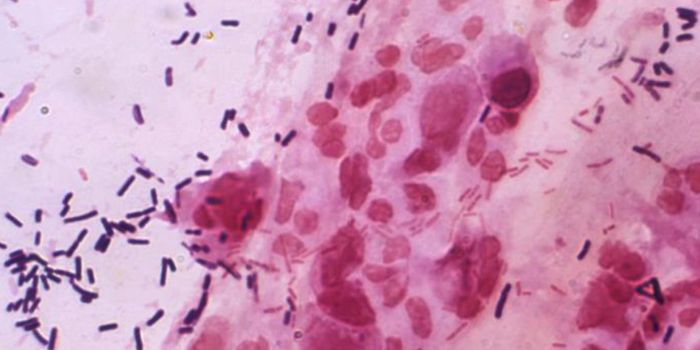

APR 19, 2022ImmunologyTuberculosis is caused by a bacterium, Mycobacterium tuberculosis, that is thought to have been around for about 150 mil ...